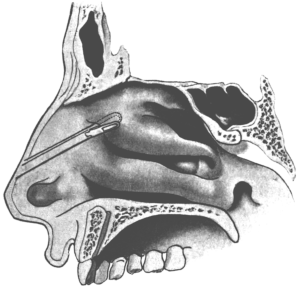

| 289. | First Step in removing the Anterior End of the Inferior Turbinal, which is seen to have undergone Polypoid Degeneration | 587 |

| 293. | First Step in the Removal of the Anterior End of the Middle Turbinal | 594 |

| 294. | Second Step in the Removal of the Anterior End of the Middle Turbinal | 594 |